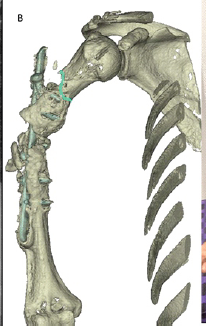

Humerus Non-union with Segmental Bone Loss Treated with 3D-printed Prosthesis: A Case Report

Sujit Jos , Rahul Chandran , Prannoy Paul , Kiran Benny , Midhun Jose

………………………………p.198-202